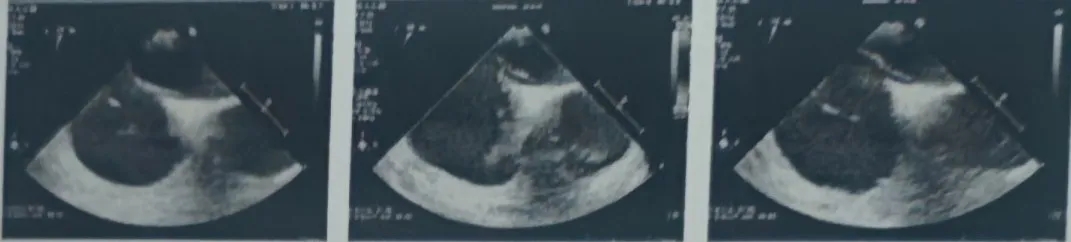

TEE超声所见:房间隔回声中断不明显,略向右心房膨出,宽度18mm,深度5mm,略有摆动,卵圆窝处较薄,未见房水平分流,左房侧开口约1.2mm,右房侧开口不明显,瓦氏动作后左房侧开口约1.5mm,右房侧开口约2.5mm,可见房水平少量左向右分流,隧道长度约12mm,继发隔厚度约3mm,右房内可见下腔静脉瓣,长度约29mm,摆动明显。

超声诊断:房间隔卵圆孔未闭,体部及耳部未见明显血栓

右心声学造影:10ml手振生理盐水,经左上肢贵要静脉快速注入,右房充分显影,静息状态第二个心动周期左心房内见中等量微泡进入,瓦氏动作后即刻左心房内见大量微泡进入。

超声提示:心房水平可见右向左分流(大量)。

术后超声

超声下可见封堵器左右盘面牢牢贴靠房间隔,且无残余分流,封堵成功